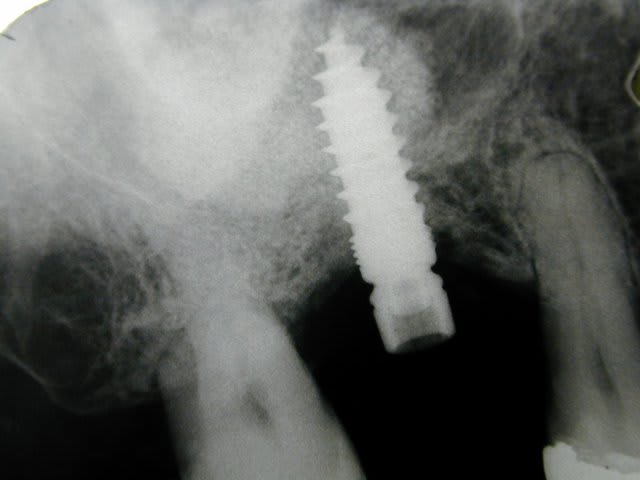

des photos d'un cas d'aujourd'hui avec le shuttle retiré ( 8 premières photos)

les 4 dernières c'est avec le foret , la dernière photo c'est un cas d'extraction implantation d'aujourd'hui aussi on voit la nouvelle alvéole après le forage ( désolé pour la qualité de photo...)